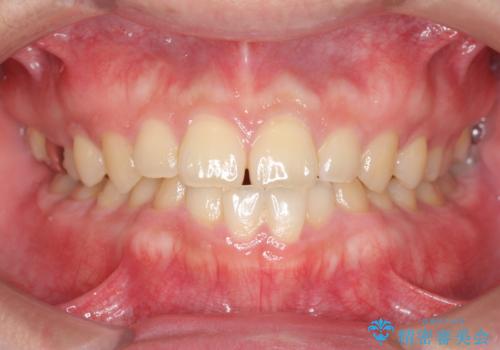

一度諦めた矯正にチャレンジしたい インビザラインとセラミック治療

少しだけ飛び出た前歯を整えたい インビザラインによる矯正治療

抜けてしまうと言われた前歯 インビザラインによる矯正治療

深いかみ合わせ 出っ歯の治療 インビザラインで

見た目だけじゃない:マウスピースでも短期間で噛み合わせと口元を改善

飛び出した前歯と黄ばんだ歯 ホワイトニングしながらマウスピース矯正

下の前歯が見えない:深い噛み合わせもインビザラインで

【モニター】前歯のデコボコをインビザラインできれいに整える

治療途中の前歯を治したい インビザライン矯正とオールセラミッククラウン

入国制限で帰国できず 海外出張中のインビザライン矯正

前歯のデコボコと突出感 インビザラインにて矯正治療

奥歯の銀歯と歯並びを改善 歯周外科治療と矯正治療を行った総合歯科診療